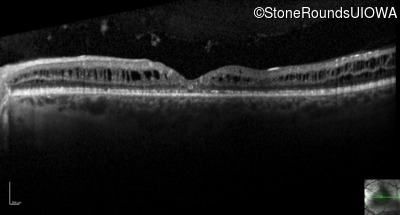

Optical Coherence Tomography - Left - 20/40

Exemplar / OCT Stack